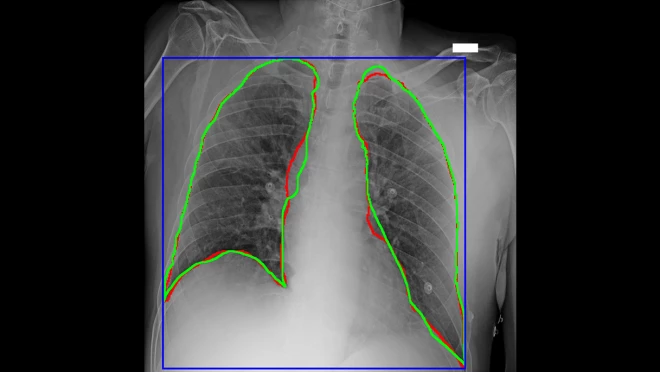

图4  AlforCOVID项目的新冠患者胸部X光片,对感染区域的AI划线(红色)与手工划线(绿色)很接近

“在对新冠患者的管理中,放射影像学对诊断和治疗方案起着至关重要的作用。得益于亚马逊云科技的技术和专业支持所带来的机器学习力量,我们已经能够快速理解诊断成像和临床分析所产生的大量数据。我们正在努力提供实用的资源,世界各地的医院和组织可以应用这种资源,增加对疾病的理解,促进自己的诊断工作,改善患者治疗。”意大利诊断中心影像诊断和立体定向放射外科主任Sergio Papa表示。